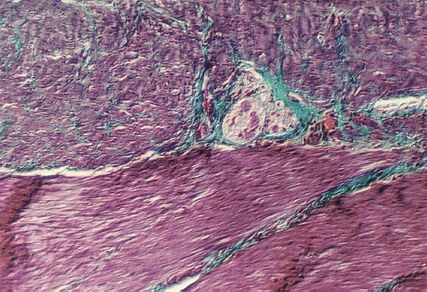

The following photographs show different views of the Auerbach's plexus in the pylorus. They are easier to find because of the Masson Trichrome stain that delineates the connective tissue (blue).